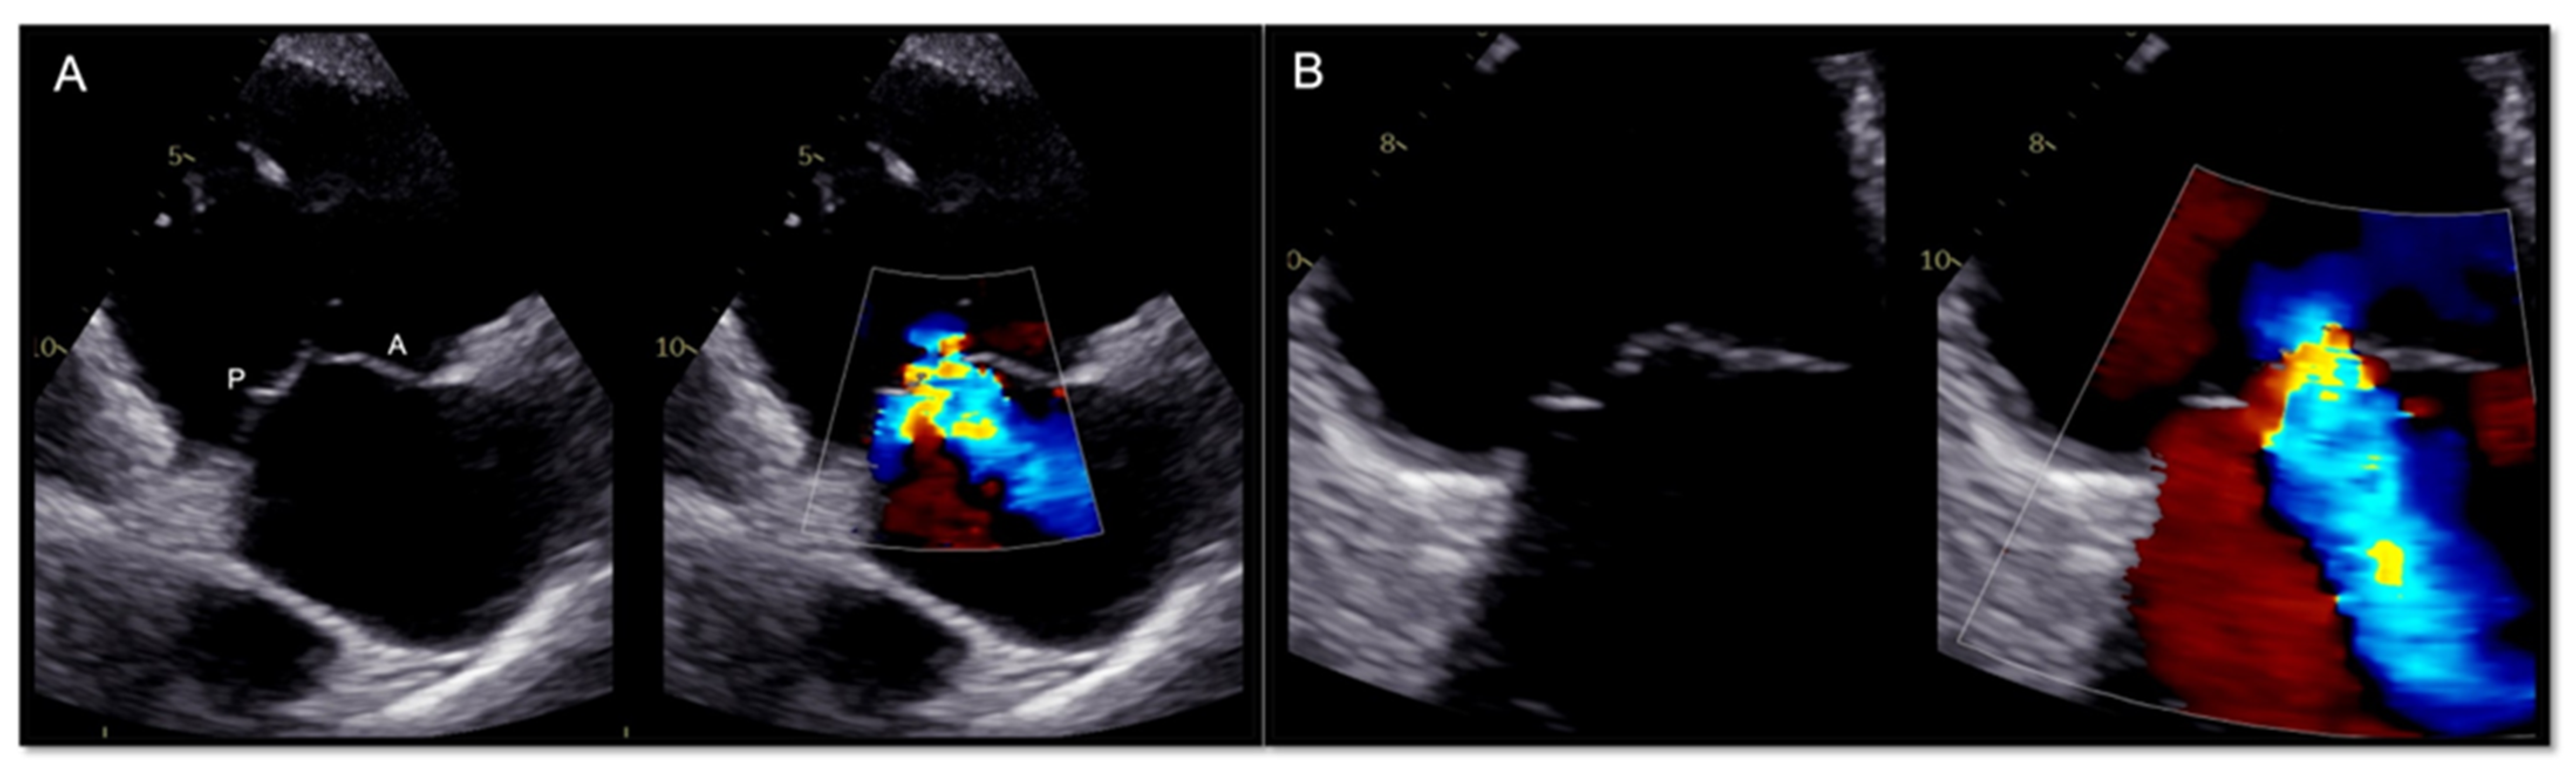

2.1. Two-Dimensional and Three-Dimensional Transthoracic and Transesophageal Echocardiography

3.1. Two-Dimensional and Three-Dimensional Transesophageal Echocardiography

- Ro, R.; Tang, G.H.L.; Seetharam, K.; Khera, S.; Sharma, S.K.; Kini, A.S.; Lerakis, S. Echocardiographic Imaging for Transcatheter Tricuspid Edge-to-Edge Repair. J. Am. Heart Assoc. 2020, 9, e015682. [Google Scholar] [CrossRef] [PubMed]

- Agricola, E.; Ancona, F.; Stella, S.; Rosa, I.; Marini, C.; Spartera, M.; Denti, P.; Margonato, A.; Hahn, R.T.; Alfieri, O.; et al. Use of Echocardiography for Guiding Percutaneous Tricuspid Valve Procedures. JACC Cardiovasc. Imaging 2017, 10, 1194–1198. [Google Scholar] [CrossRef]